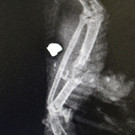

Brieftaube_2.jpg

Download Photo (1024 x 683)

Wiener+Tierschutzverein

Datum: 20.09.2017

Betrachtungen: 1